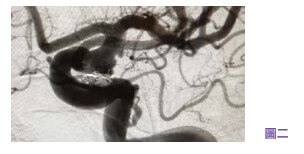

三维立体的脑血管动态造影显示,病人大脑左边的后交通动脉有一个爆破了的血管瘤,需要做紧急微创导管手术,脑血管外科医生利用金属丝将脑动脉瘤出血的位置堵塞止血(见图二),防止它在短时间内再次破裂,接着再用药物减低病人的颅内压。 幸好出血性中风对病人大脑的伤害并不严重,病人在手术后两天甦醒过来,经过三星期的休养便康复出院。 三个月后专科医生再为病人植入血液扰流导向支架,将动脉瘤剩余的空间完全封闭(见图三),顺利将脑内剩余的炸弹拆除殆尽后,病人再无后顾之忧。